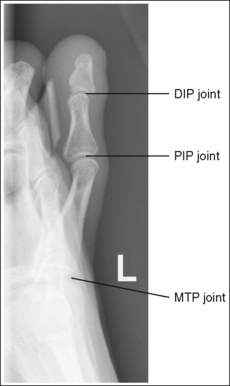

See Figures 6-1, 6-2, and 6-3 and Box 6-2.

FIGURE 6-1 First AP axial toe projection with accurate positioning. DIP, Distal interphalangeal; MTP, metatarsophalangeal.

The digit demonstrates no rotation. Soft tissue width and midshaft concavity are equal on both sides of the phalanges.